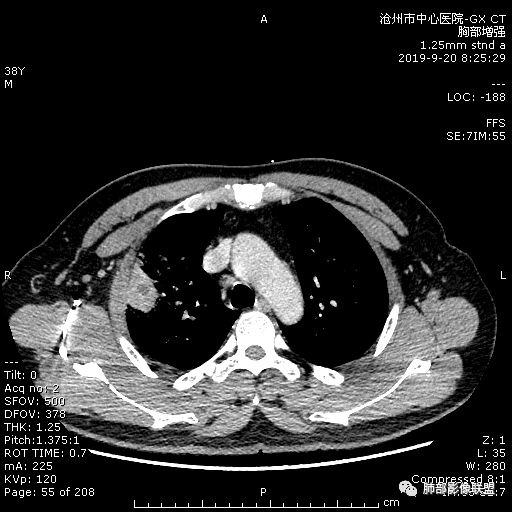

年轻男性,咳嗽2月,痰中带血,胸痛,炎症指标稍高,肿标正常。影像,右肺上叶不规则团块影,浅分叶,伴边界不清磨玻璃影,从外周向内分布,局部胸膜增厚,病灶中央坏死,坏死边界尚清,空洞形成,空洞内壁光滑;考虑炎性肉芽肿性病变,结核可能,鉴别恶性肿瘤及真菌感染。病灶分布特点不考虑隐球。

右肺上叶不规则病灶,密度不均,有分叶,边缘不清,中央有坏死,坏死壁尚光滑,增强壁有强化,病灶有外朝内,整体收缩为主,慢性病程,考虑炎性病变,肺脓肿或者结核,淋巴结肿大,支气管截断,胸膜脂肪间隙变窄,加个鉴别恶性肿瘤。

38岁,男性,慢性咳嗽2月,右胸痛8天,无发热;白细胞高,肿瘤标志物不高;右上肺不规则块状影,周围有磨玻璃影,边界清,整体有膨胀感,分叶,与胸膜糊墙,并见栽赃,增强肿块中央坏死,周边强化。综合考虑,考虑恶性,鳞癌可能。

38岁,男性,慢性咳嗽2月,右胸痛8天,无发热。白细胞高,肿瘤标志物不高。右上肺不规则块状影,周围有磨玻璃影,边界模糊,整体有膨胀感,分叶,与胸膜糊墙,可疑栽赃,增强肿块中央坏死,边界清,周边强化明显,强化区有低密度影,壁不规则,跨叶生长,支气管截断,伴支气管扩张,综合考虑腺癌

中年男性,咳嗽2月,伴胸痛8天,少许痰血,无发热中性粒明显增高,低氧,肿标不高,右肺上叶不规则实性肿块,深分叶,局部凹陷呈月牙铲改变,多坏死,多空泡,前段支气管分支似见堵塞,2R、4R、10R和7区淋巴结肿大。考虑肺癌可能,建议支气管镜活检

3.ct表现:肺脓肿可呈结节状或团块状,有时呈不规则形,气道来源肺脓肿常单发,血行来源常多发,边缘模糊,部分病灶周围可见片状肺实变及磨玻璃影;病灶中央为液化坏死区,若脓肿与支气管相通,脓液排出可形成空洞,空洞内可形成液平;急性肺脓肿内壁多不规则;慢性肺脓肿洞壁较厚,一般不规则或形成多房空洞:CT增强扫描空洞壁可见强化,空洞壁为纤维肉芽组织,呈典型的环形强化;慢性肺脓肿周围可有较广泛的纤维索条影,可伴支气管扩张.肺

气肿或胸膜增厚表现。

今天病例坏死周围也可以看到明显强化的脓肿壁,只是局部脓肿壁不规则模糊,部分脓肿壁规则清楚。